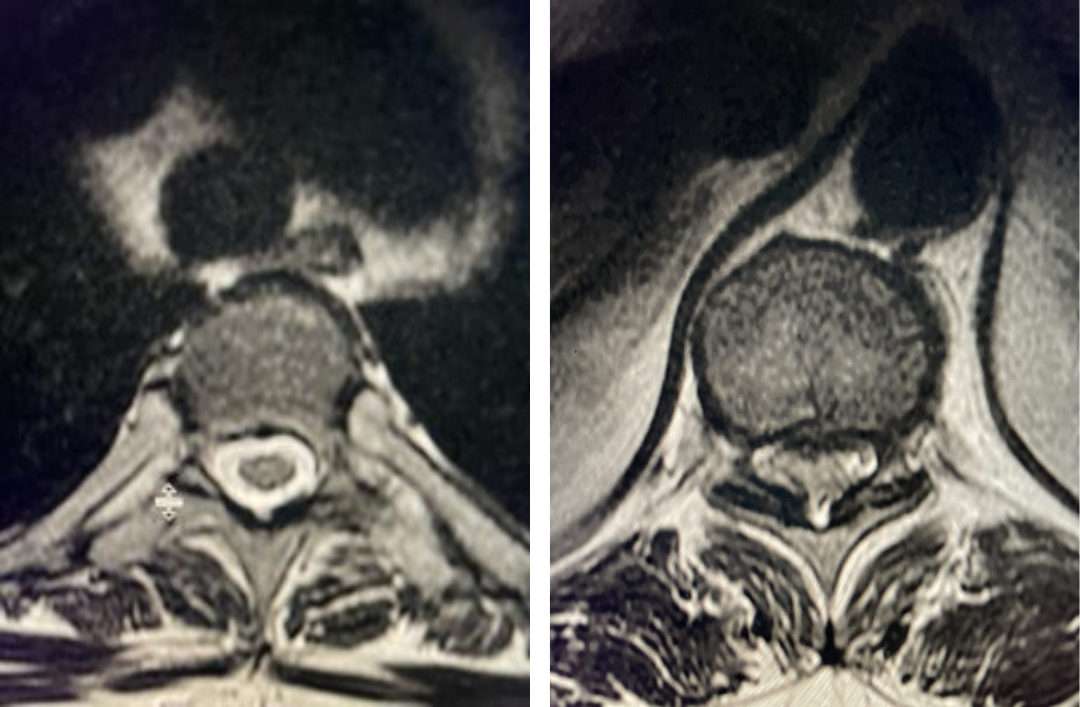

This 63-year-old female presents with nine months of low back pain and pain radiating to the lower extremities with the left leg worse than the right. The patient complained of numbness and tingling as well. The pain was exacerbated by standing, walking, and coughing. An MRI demonstrated severe lumbar stenosis L3-L5 with a superimposed left L3-4 synovial cyst (Fig 1).

Fig 1: Sagittal and axial T2-weighted MRI images demonstrating a large superiority-oriented synovial cyst (red arrow) at L4-5. The cyst is below the exiting L4 nerve root and hence compresses the descending L5 root. Note the additional thickened ligamentum flavum and slight spondylolistheses at L3-4 and L4-5 (blue arrow).

The patient also had a slight spondylolisthesis at L3-4 and L4-5. The patient failed all means of conservative management including medications, physical therapy, and epidural injections. The patient elected to proceed with a decompressive laminectomy and in-situ fusion. During the procedure we encountered a thick-walled cyst that melded with the dura. We first found the descending left L4 nerve root and separated the cyst and proceeded to in essence bite away the cyst with an instrument. We decompressed the L4 nerve root as it entered its foramina by removing the majority of the cyst wall. There was thick gray gelatinous material within the cyst. Part of the cyst wall seemed to be continuous with the dura and left it alone as it caused no pressure on the root. After our decompression we decided to perform an in-situ fusion as we had relative preservation of the joint complexes. Post operatively, she had an uneventful course with significant relief of her leg pain.